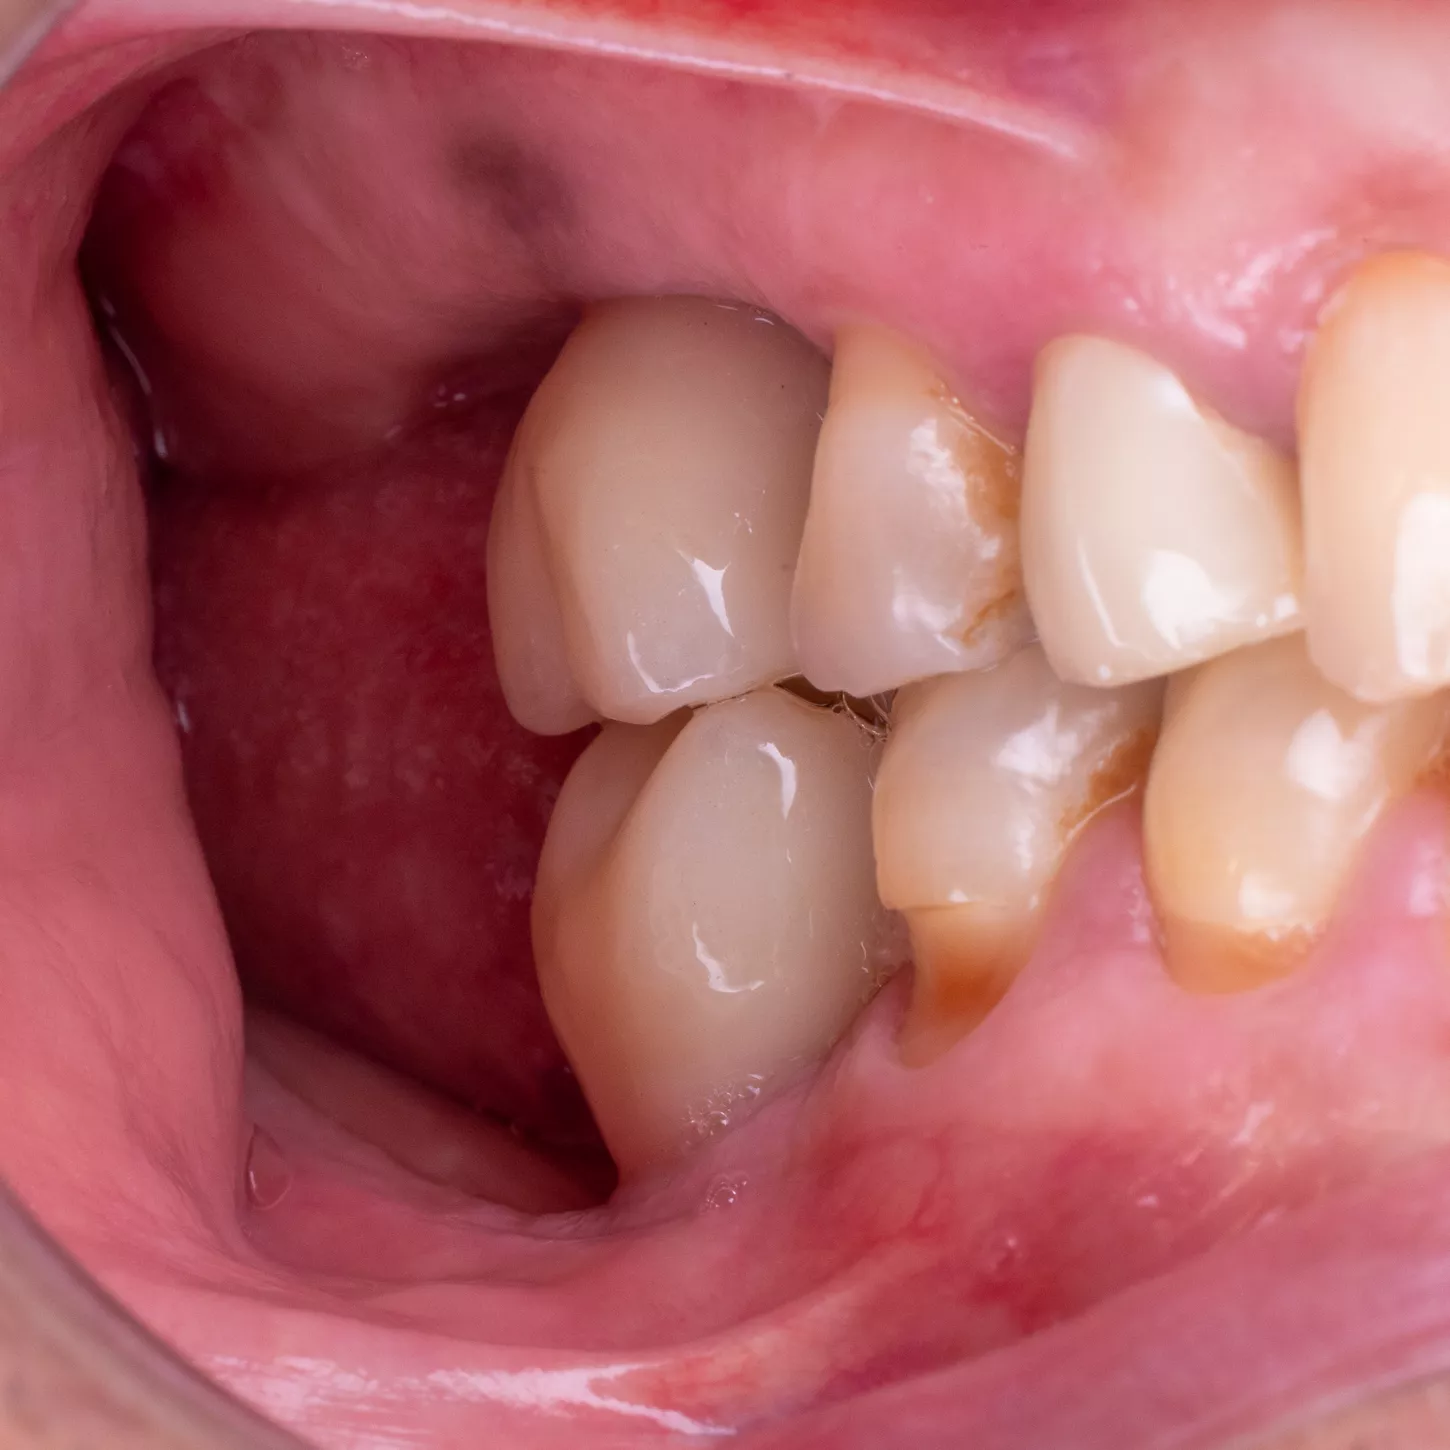

24. 25. 25. 27.

Clinical views of the implant-supported prosthesis 4 months after fitting. Lateral views in occlusion and occlusal views.